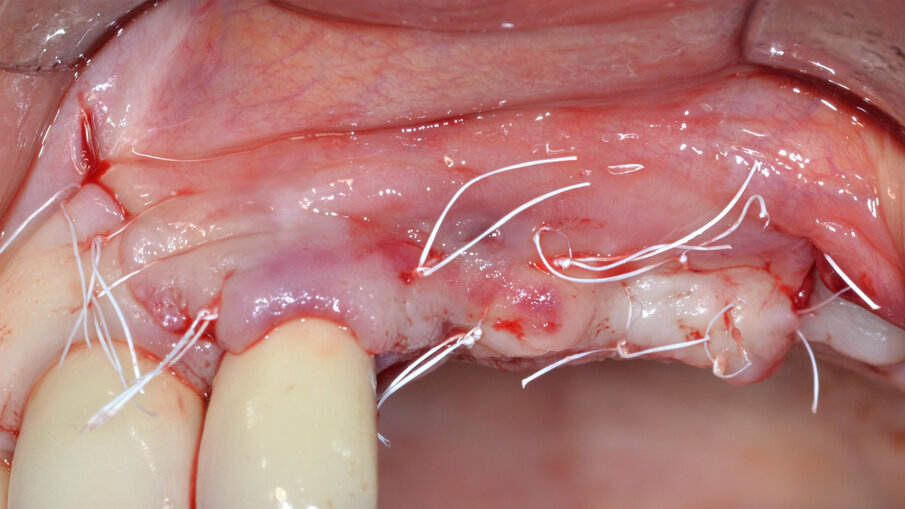

L’ultimo tempo operatorio prevede una doppia linea di sutura consistente in punti a materassaio orizzontale interno intercalati a punti staccati effettuata con un filo in PTFE 5/0 (Profimed, Resista) (Fig. 11). Durante il follow-up a distanza di 30 giorni è possibile evidenziare la perfetta guarigione dei tessuti molli con assenza di esposizione della membrana; va sottolineato come questa evenienza rappresenti la più frequente e temibile complicanza nelle procedure di rigenerazione guidata. Dopo 6 mesi di guarigione indisturbata, al momento del rientro chirurgico l’impianto appare circondato da una soddisfacente quantità di tessuto neoformato e il difetto completamente riempito (Fig. 12).

Fig. 10 - Sutura con punti a materassaio orizzontale interni intercalati a punti staccati.